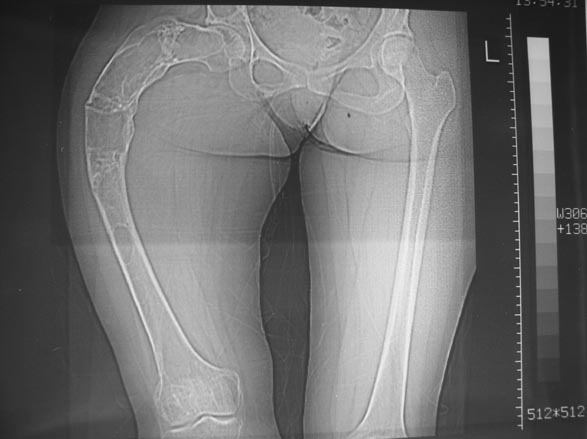

Женщина 28 лет, Больна с 12 летнего возраста, Когда после адекватной травмы получила перелом бедра. На рентгенограммах выявлено какое-то (рентгенограмм и документов нет) изменение бедренной кости, была оперирована, имеется гистологическое заключение - фиброзная дисплазия.дСформировалась деформация бедра. На сегодня - Укорочение 7см. Грубая деформация бедра по типу "пастушьей палки", последний патологический перелом в январе 2004г., консолидировавшийся при консервативном лечении. Имеются грубые изменения и в надвертлужном массиве.-- С уважением, Leonid

Хотелось бы показать, что получилось в результате.

Операция выполнялась с помощью А.Н.Челнокова. Очень понравилась технология выполнения блокируемого остеосинтеза с использованием спицевого дистрактора, модифицированный гвоздь с латерализованным проксимальным отделом и возможностью многовинтовой фиксации проксимального и дистального участков бедра.